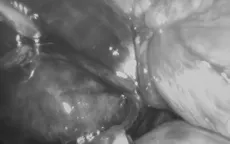

Sốc nhiễm trùng nguy kịch do viêm túi mật hoại tử VTV.vn - Trung tâm Y tế huyện Vân Đồn (Quảng Ninh) vừa phẫu thuật cấp cứu kịp thời cho 1 bệnh nhân bị viêm túi mật hoại tử do sỏi có biến chứng sốc nhiễm trùng, nhiễm độc.